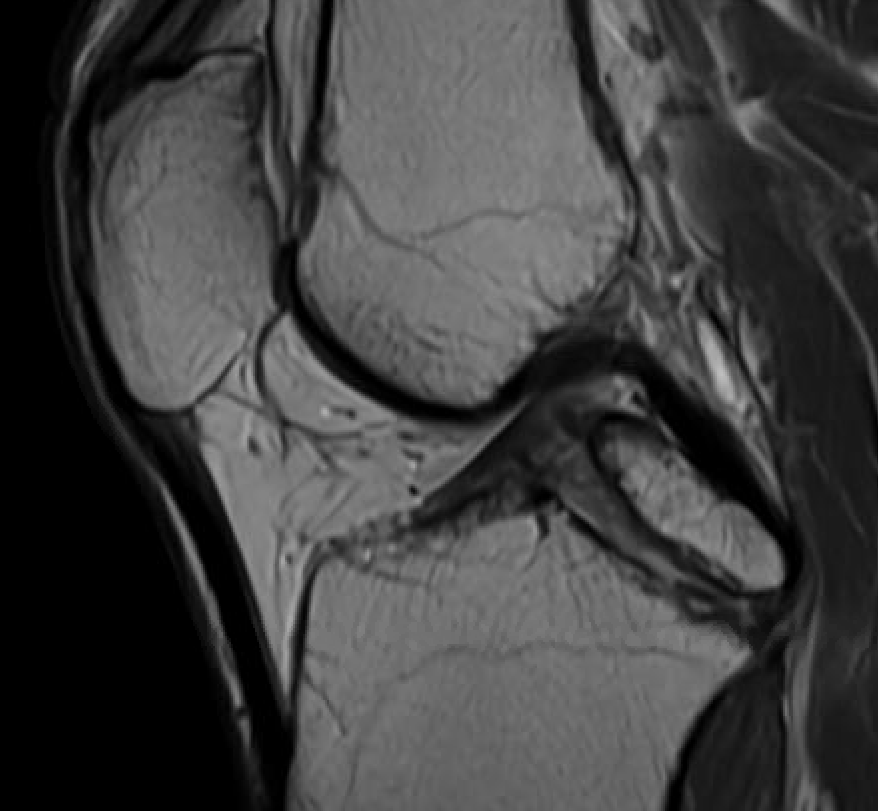

MRI

PCL completely torn

PCL midsubstance tear with lengthening

PCL tibial avulsion

PCL femoral avulsion